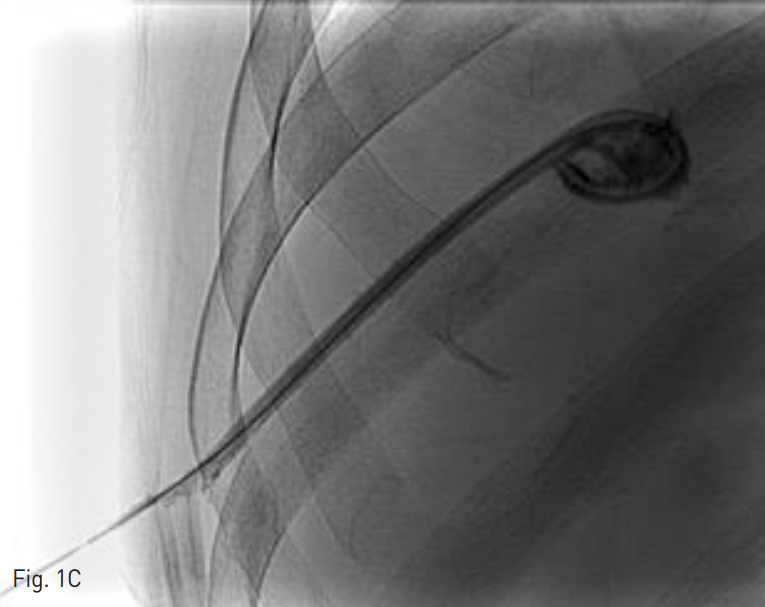

Fig. 1. A 65-year-old man who underwent pig-tail catheter insertion for the right hepatic abscess.

B-C. A Terumo guide wire was inserted along the tract, and the tip of guide wire was located in the abscess pocket.